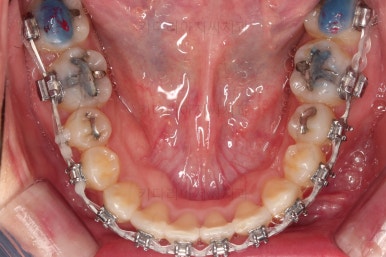

치료 종료 시 입안의 모습입니다.

윗니만 발치를 했지만 교합이 잘 맞고요.

한 쪽 송곳니가 없지만 기능적으로 전혀 문제를 못느끼실 교합을 맞춰놨고요.

위아랫니 가지런해졌고요.

대신 중앙선은 약간 틀어져 있는데요.

한 쪽은 송곳니가 없고 한 쪽은 작은 어금니를 발치했기 때문인데요.

18개월이라는 짧은 기간동안 부정교합, 덧니, 심지어 매복치아까지 개선했는데 양측 치아 사이즈 문제로 생기는 중앙선 정도는 아무 문제가 안되는거죠.